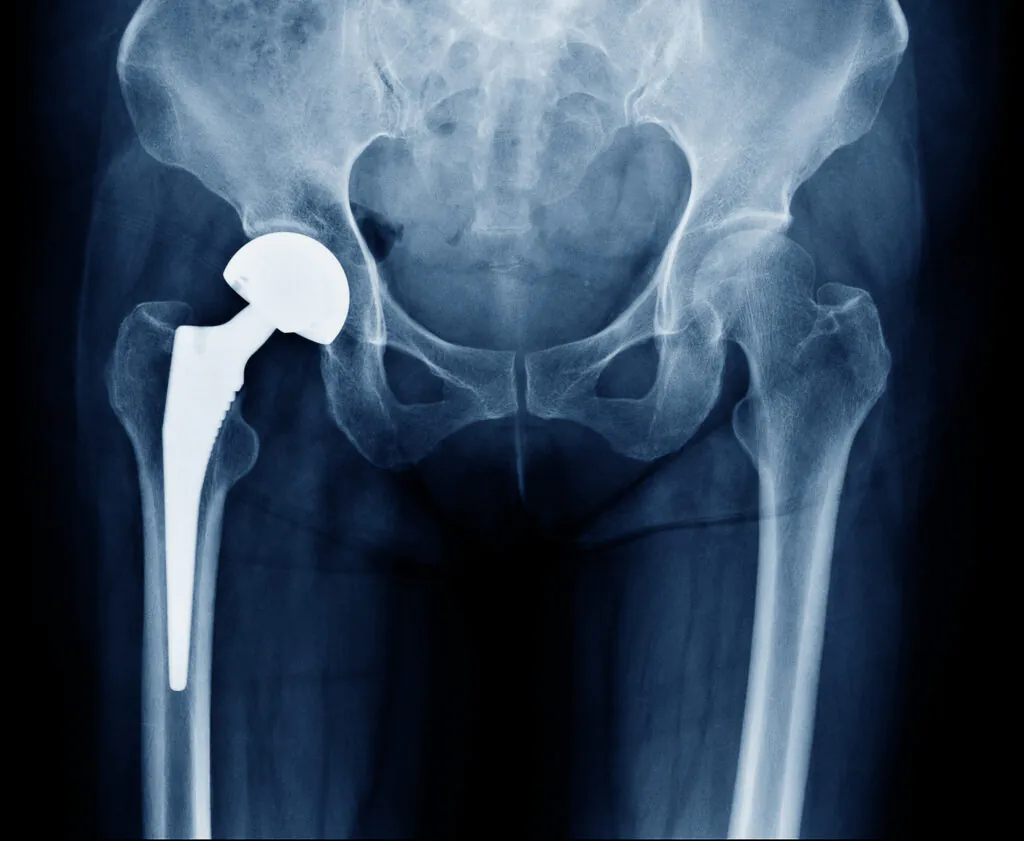

X-ray scan image of hip joints with orthopedic hip joint replacement or total hip prosthesis on right side implant head and screws in human skeleton in blue gray tones.